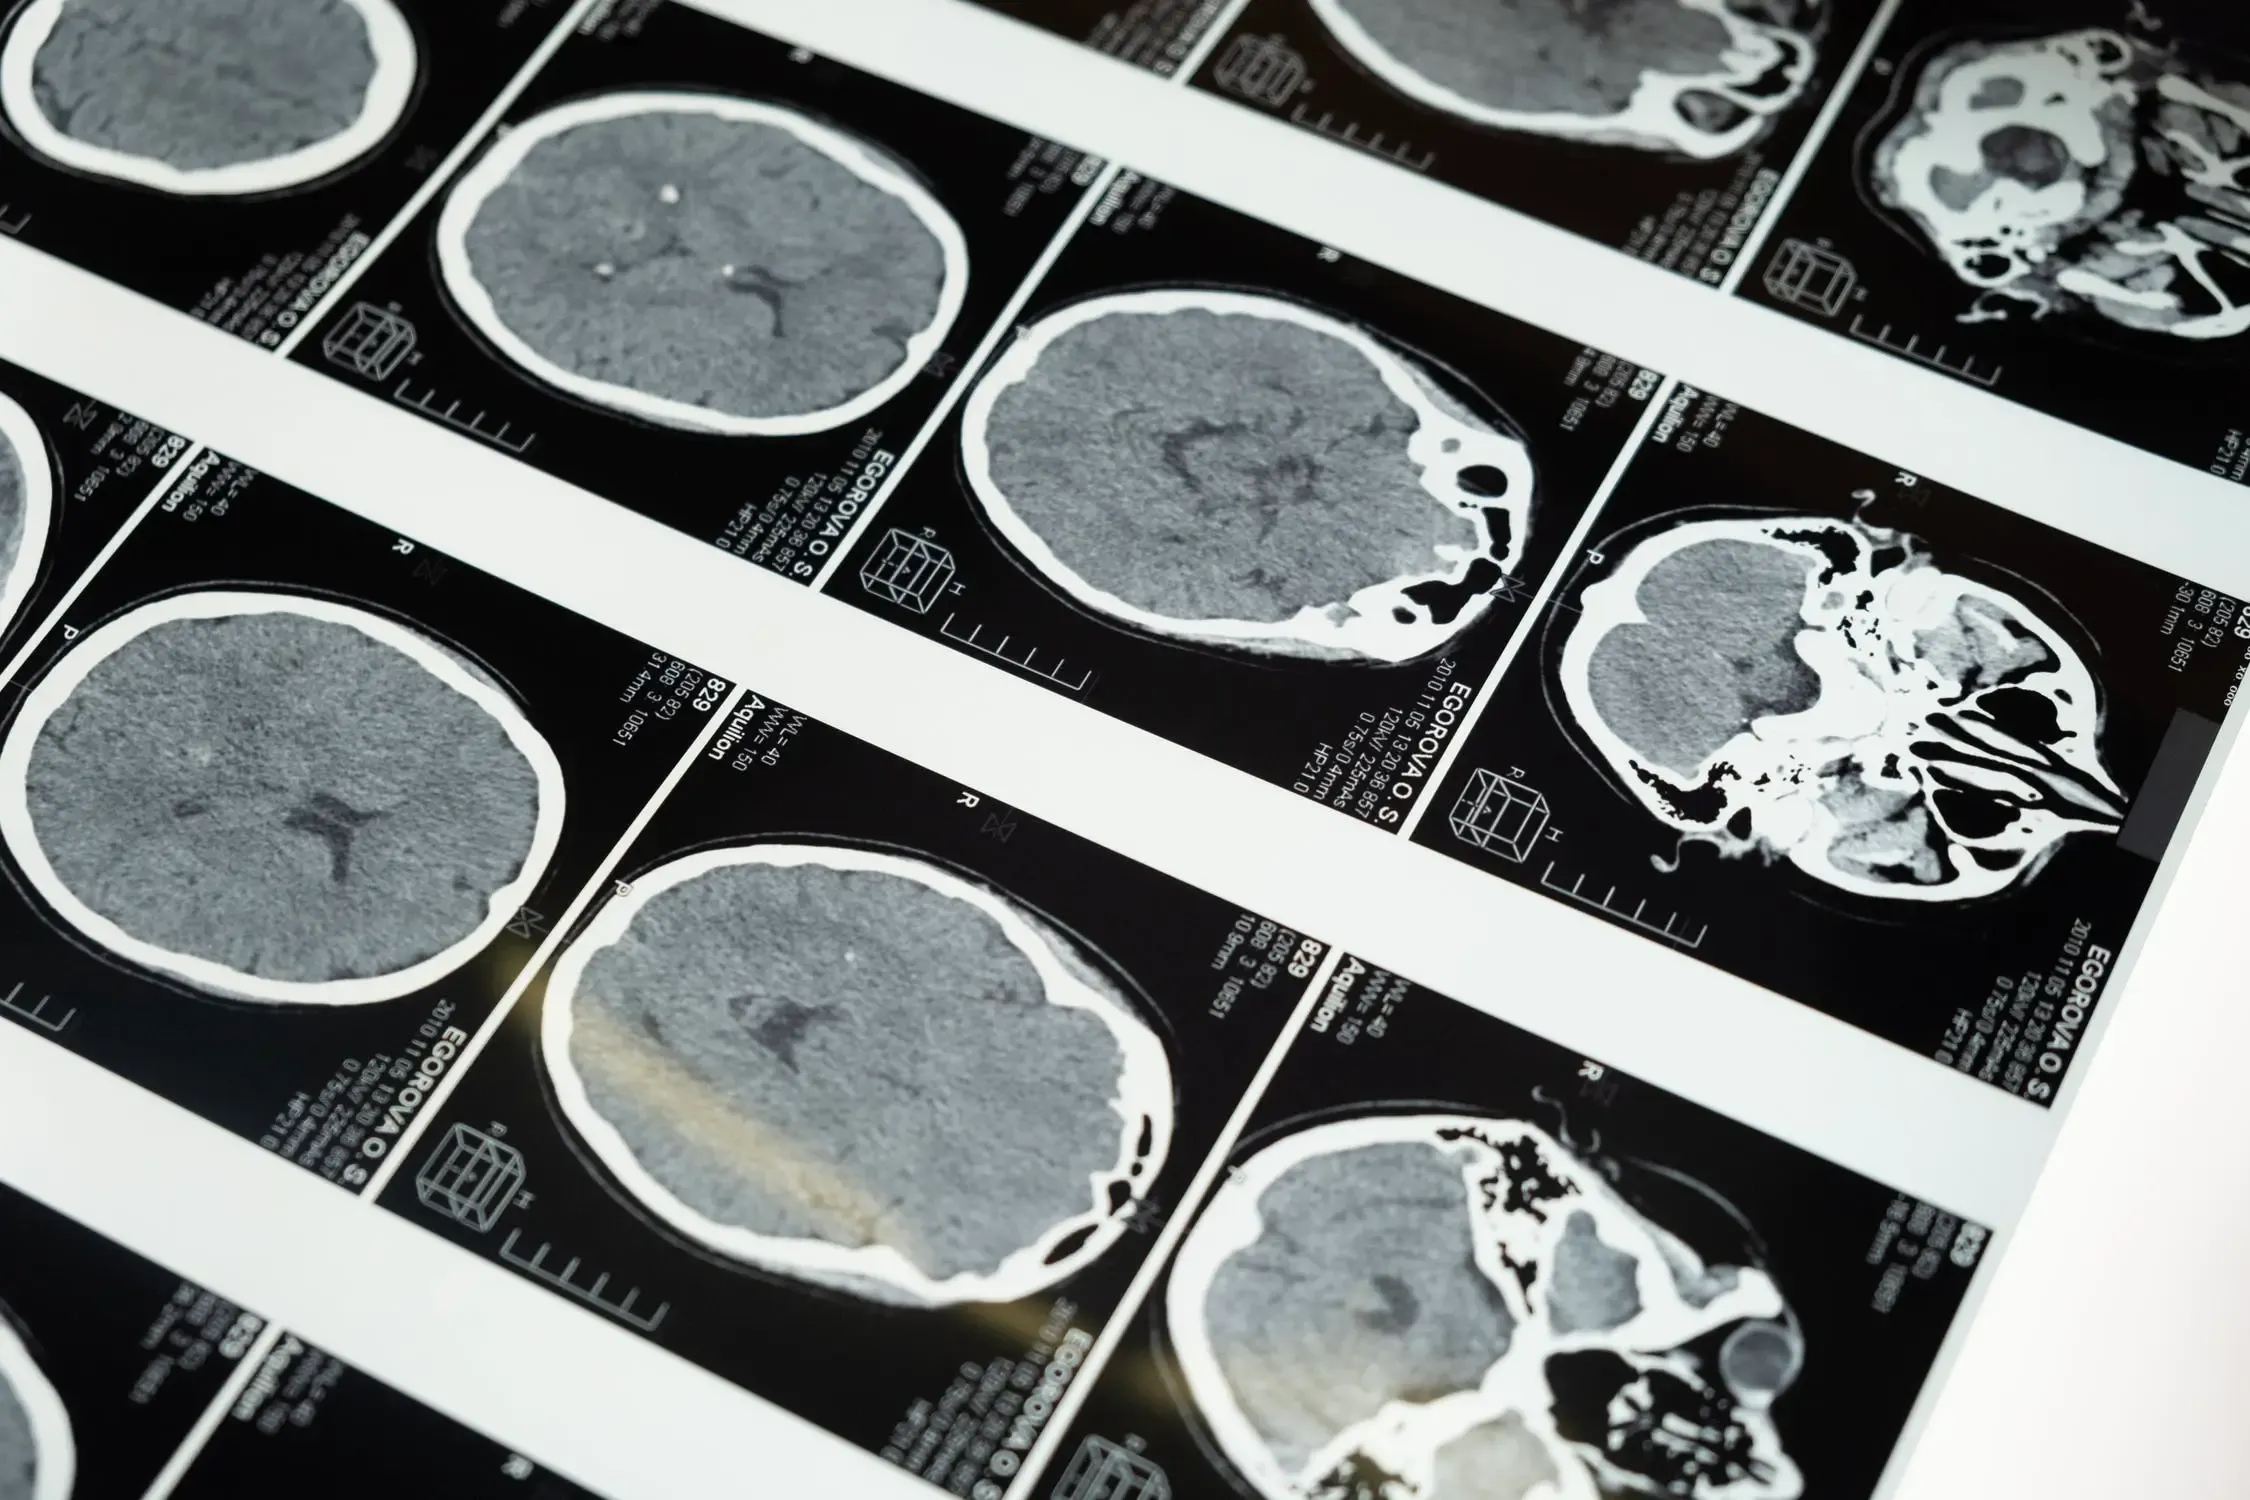

I soon started working on machine learning algorithms for medical imaging. Wrote papers on if neural networks can help us find new patterns in diseases given a huge corpus of data. It was interesting, but then the real problem hit me.

Healthcare data is very different from, for example, the data that internet companies generate. First, every single point of healthcare data generated for a patient costs money. A doctor’s opinion: ₹200. An X-ray: ₹800. An MRI: ₹8,000. The patient pays for each data point that is collected. Compare this to the data collected from your mouse movements by a company like Google or Facebook — the user pays nothing. Second, healthcare data is rich in information. Every single data point is representative of a disease and a patient. It is very easy to profile and learn from disease patterns given a diagnosis. And third, the payoff for utilizing data-driven decisions in healthcare is immense. It could mean a better outcome and a longer life span for a person.